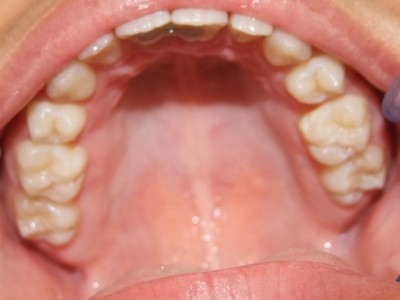

Behandeling Hajar

Beschrijving

Leeftijd bij aanvang: 9 jaar

1-6 maanden Bonded Hyrax in de bovenkaak, banden/slotjes in de onderkaak met Transforce